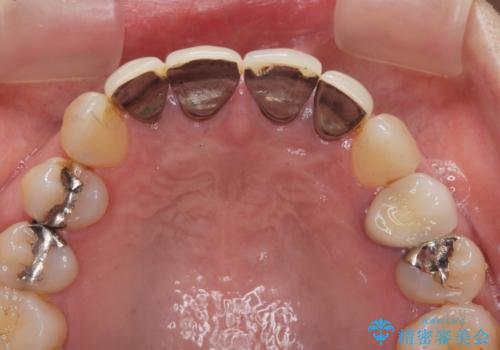

- 「黒ずみの前立つ前歯をやりかえ、きれいにしたい。」と希望され来院されました。

金属色の目立つ前装冠を除去し、発生していた小さな虫歯を丁寧に全て除去しジルコニアセラミッククラウンで審美的な前歯となるような治療を計画します。